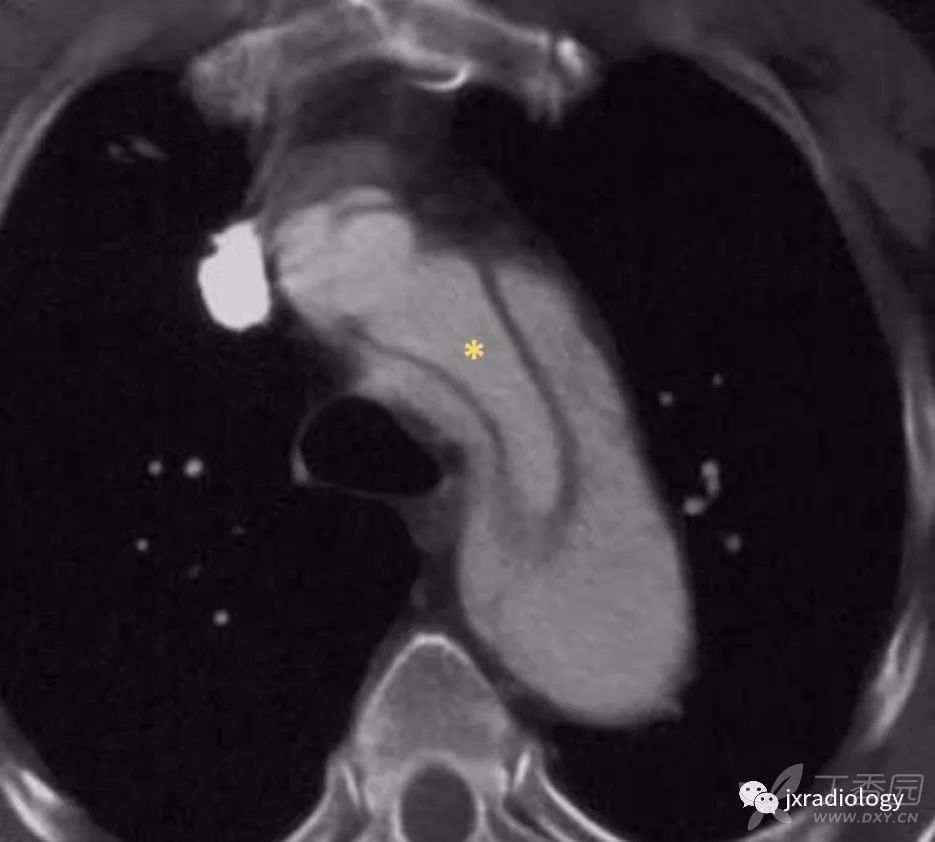

内膜内套叠是一种环状的主动脉夹层,类似于风向袋( 图10 )。在这些情况下,内膜撕裂通常位于冠状动脉开口附近,通常内腔是真腔。

图10:增强CT显示内膜套叠。

一种特殊类型的主动脉夹层,主动脉壁内膜呈圆形分离。内腔是真腔(星号)。